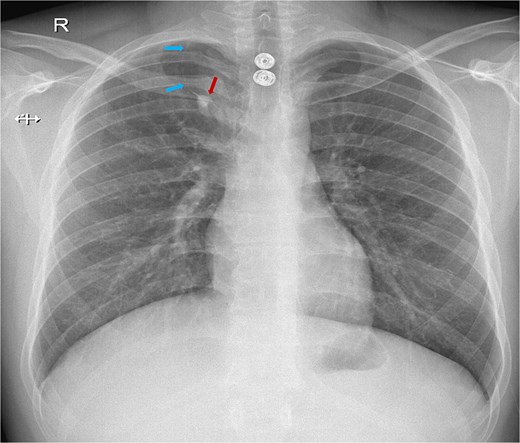

As part of the trauma protocol, a supine chest X-ray (CXR) was obtained. The trauma team suspected a pneumothorax based on the imaging showing a longitudinal lucency along the right apical area (Fig. 1). A minor right apical pneumothorax or, less commonly, a radiopaque foreign body artifact was initially suspected during radiographic assessment. A contrast-enhanced CT scan of the chest was promptly acquired due to the high-risk mechanism and the possibility of concealed thoracic injury.

Chest X-ray showing a white line crossing from the lateral to the medial side of the right upper lung. The blue arrows indicate the azygos fissure, while the red arrow points to the azygos vein located at the base of the fissure with the characteristic ``tear drop'' sign.

The azygos vein invaginates across the right upper lung during embryonic development, forming the azygos fissure, a four-layered pleural reflection that gives rise to the azygos lobe. This fissure has a distinctive inferomedial trajectory toward the right tracheobronchial angle and manifests as a thin, curvilinear opacity on CXR [3, 4]. This feature was first misidentified as a pneumothorax in our patient (Fig. 1). Previous investigations have reported similar diagnostic errors, where the appearance of the azygos lobe has been misinterpreted as other pulmonary conditions [3].